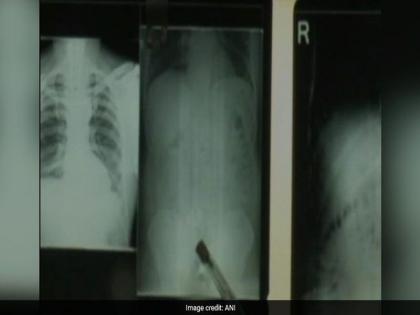

त्याच्या या जबाबानंतर सगळेच आश्चर्यचकित झाले. सोन्याची बिस्किटे घेऊन एवढ्या लांबून प्रवास करूनही तो प्रवासी अगदी व्यवस्थित होता. त्यामुळे त्याला विझाग येथील किंग-जॉर्ज हॉस्पिटलमध्ये एक्स-रे काढण्यासाठी रवाना करण्यात आले. एक्स-रेच्या रिपोर्टसमध्ये त्याच्या पोटात सोन्याची बिस्किटे असल्याचे स्पष्ट झाले. विशेष म्हणजे कोणत्याही शस्त्रक्रियेशिवाय डॉक्टरांनी त्याच्या पोटातील सोन्याची बिस्किटे बाहेर काढली. डॉक्टरांनी दिलेल्या माहितीनुसार, त्या प्रवाशाने आधी ७ बिस्किटे आणि नंतर ७ बिस्किटे खाल्ली होती. या प्रवाशाची तब्येत आता व्यवस्थित असून पुढील चौकशीकरता कस्टम्स अधिकाऱ्यांना सुपूर्द करण्यात येणार आहे. पोटाच्या आतून कोणत्याही प्रकारची तस्करी केल्याचा हा प्रकार भारतात पहिल्यांदाच झाल्याने सगळ्यांच्याच भुवया उंचावल्या आहेत.